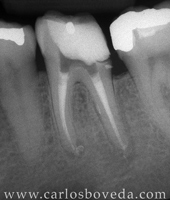

Retratamiento de Conductos en Una Sesión - (formato Quicktime)